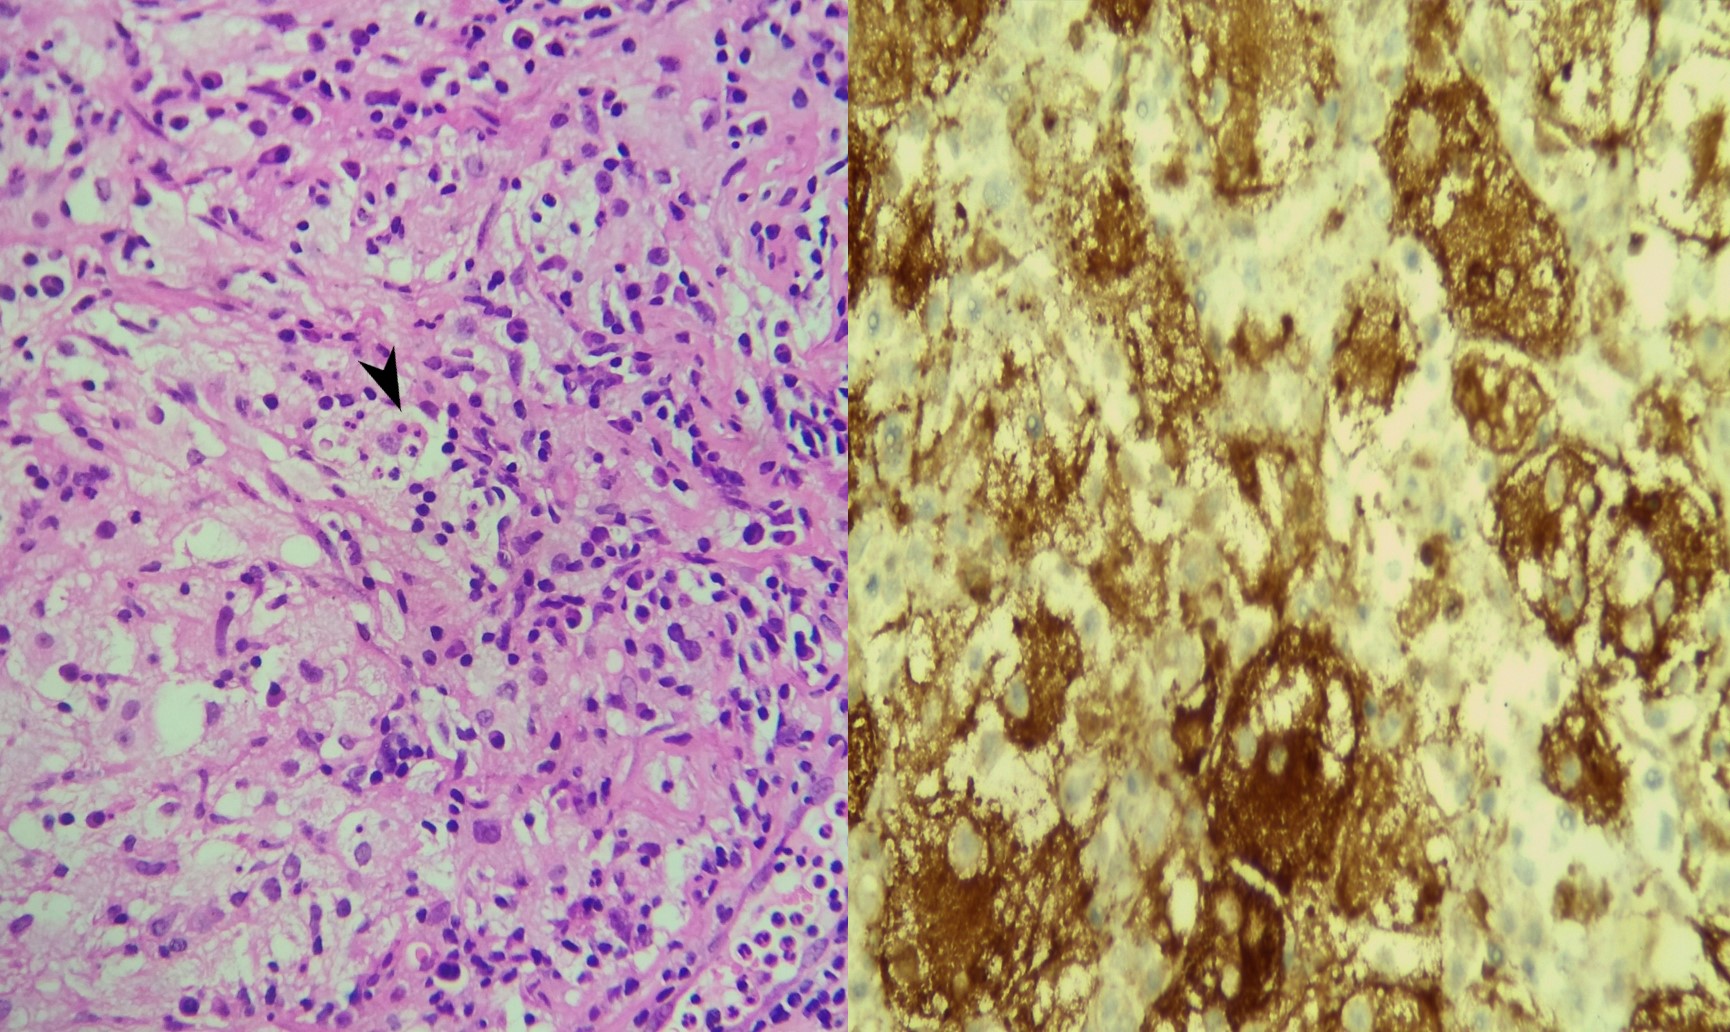

Findings Extremity X rays taken at the time of presentation to revealed lytic lesions in the metatarsal and the calcaneum. Subsequently she underwent a PET CT which revealed multifocal right breast lesions in the upper inner quadrant (White arrow heads) with right internal mammary node (white arrow) and sternal lesion (white star ).Bilateral axillary nodal uptake(solid black arrows)was seen along with multiple other lytic bony lesions (block black arrows ) Pre -biopsy Right mammogram (RCC) showed a larger spiculated and smaller irregular masses in the upper inner quadrant (Black arrow heads) .Axillary nodes showed diffuse cortical thickening on USG (black arrow),which were concerning for metastasis.Core biopsy specimen stained with H&E (x 400) demonstrated diffuse dense infiltration by lymphocytes, plasma cells and histiocytes. Emperipolesis- meaning phagocytosis of lymphocytes by histiocytes (Black arrow head) was seen in the samples.Immunohistochemistry revealed histiocytes demonstrating positivity for S100(x 400)